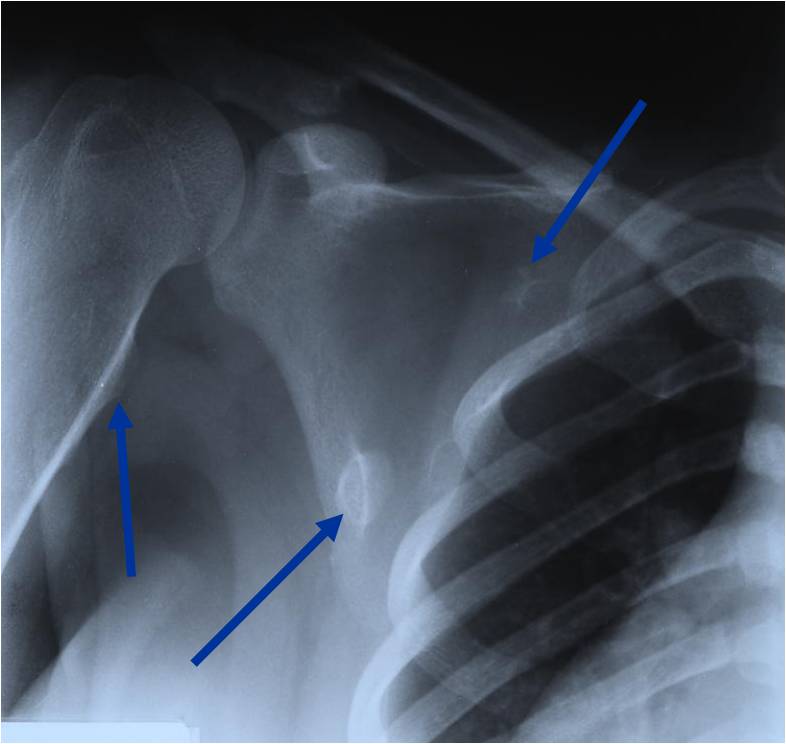

Plain X-ray: Secondary Chondrosarcoma of Proximal Femur

Radiographic Presentation

Plain X-rays:

- Projects from bone with narrow (pedunculated) to broad (sessile) stalk

- Corticomedullary continuity: Medullary bone continuous with that of osteochondroma and cortex blends with that of osteochondroma

- Calcification in cartilaginous cap (“Ring and Arc” and stippled calcifications)

- Lobular growth pattern

- Long bones: arise from metaphysis, grows away from epiphysis toward diaphysis,

- Flat bones: tend to be larger and sessile, variable appearance